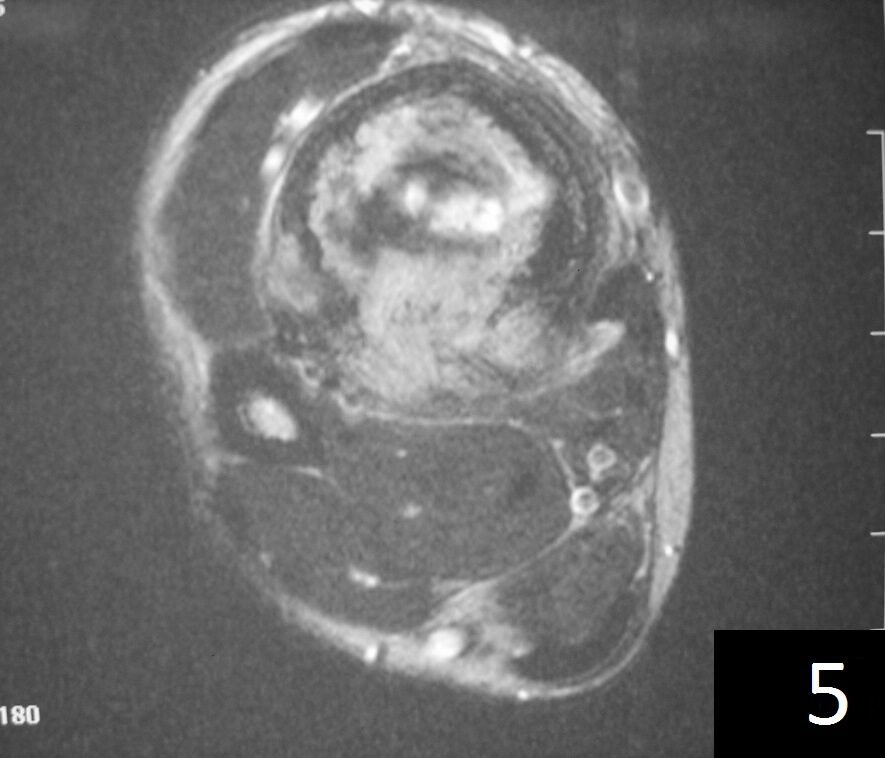

MRI (Fig. 4-5)

Fig. 5

Fig. 4-5: Axial MRI of leg demonstrates a tibia lesion with cortical destruction and soft tissue involvement.